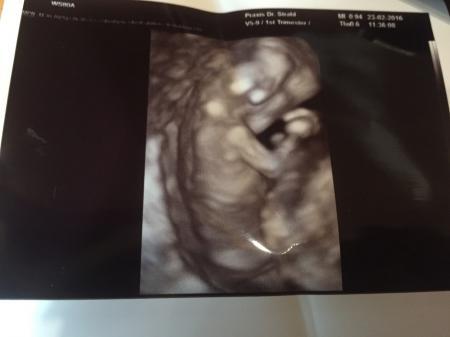

Da bin ich dann von meinem zweiten Arztbesuch zurück. Laut letzter Mens und Zyklus Länge wäre ich bei 11+6, bin laut Arzt bei 11+3 Alles tip top, in 2 Wochen um 2,25cm gewachsen. Mein kleiner Alien hat nun 4,95 cm. Mutterpass erhalten. Freude kann ich noch immer nicht wirklich zeigen, irgendwie entwickelt sich bei mir langsam eine Ss Depression, was nun auch erstmal überwacht wird. Nackenfalte hat er gemessen, liegt bei 1,1 Das hat er automatisch von sich aus mit gemacht. Bildchen gibt es bei uns jedes Mal, hänge ich mit an. Wurm wollte sich nicht drehen, gibt also eine schöne Rückansicht.... Der Arzt ist mehr als zufrieden, und seine Waage ist mir sehr sympathisch, dort bin ich nämlich 2kg leichter als zu Hause &514;

Bild zu Vom Arzt zurück - Forum für September - Mamis